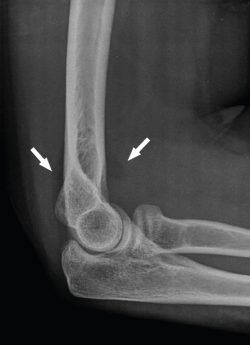

Se solicitarán radiografías simples (Rx) anteroposterior (AP) y lateral. También pueden ayudar las proyecciones oblicuas. En fracturas de la cabeza del radio no desplazadas podemos ver un signo indirecto de hemartros en el perfil estricto, la distensión de las almohadillas grasas anterior y posterior o “signo de la vela” (Figura 1). En casos de inestabilidad asociada podremos ver subluxación de la cabeza del radio respecto al cóndilo humeral. Si hay sospecha de lesión de la membrana interósea solicitaremos Rx posteroanteriores (PA) de ambas muñecas (en posición neutra) y podremos ver variaciones a nivel cubital distal.

Figura 1. Signo de la vela: distensión de las almohadillas grasas anterior y posterior por el hemartros.